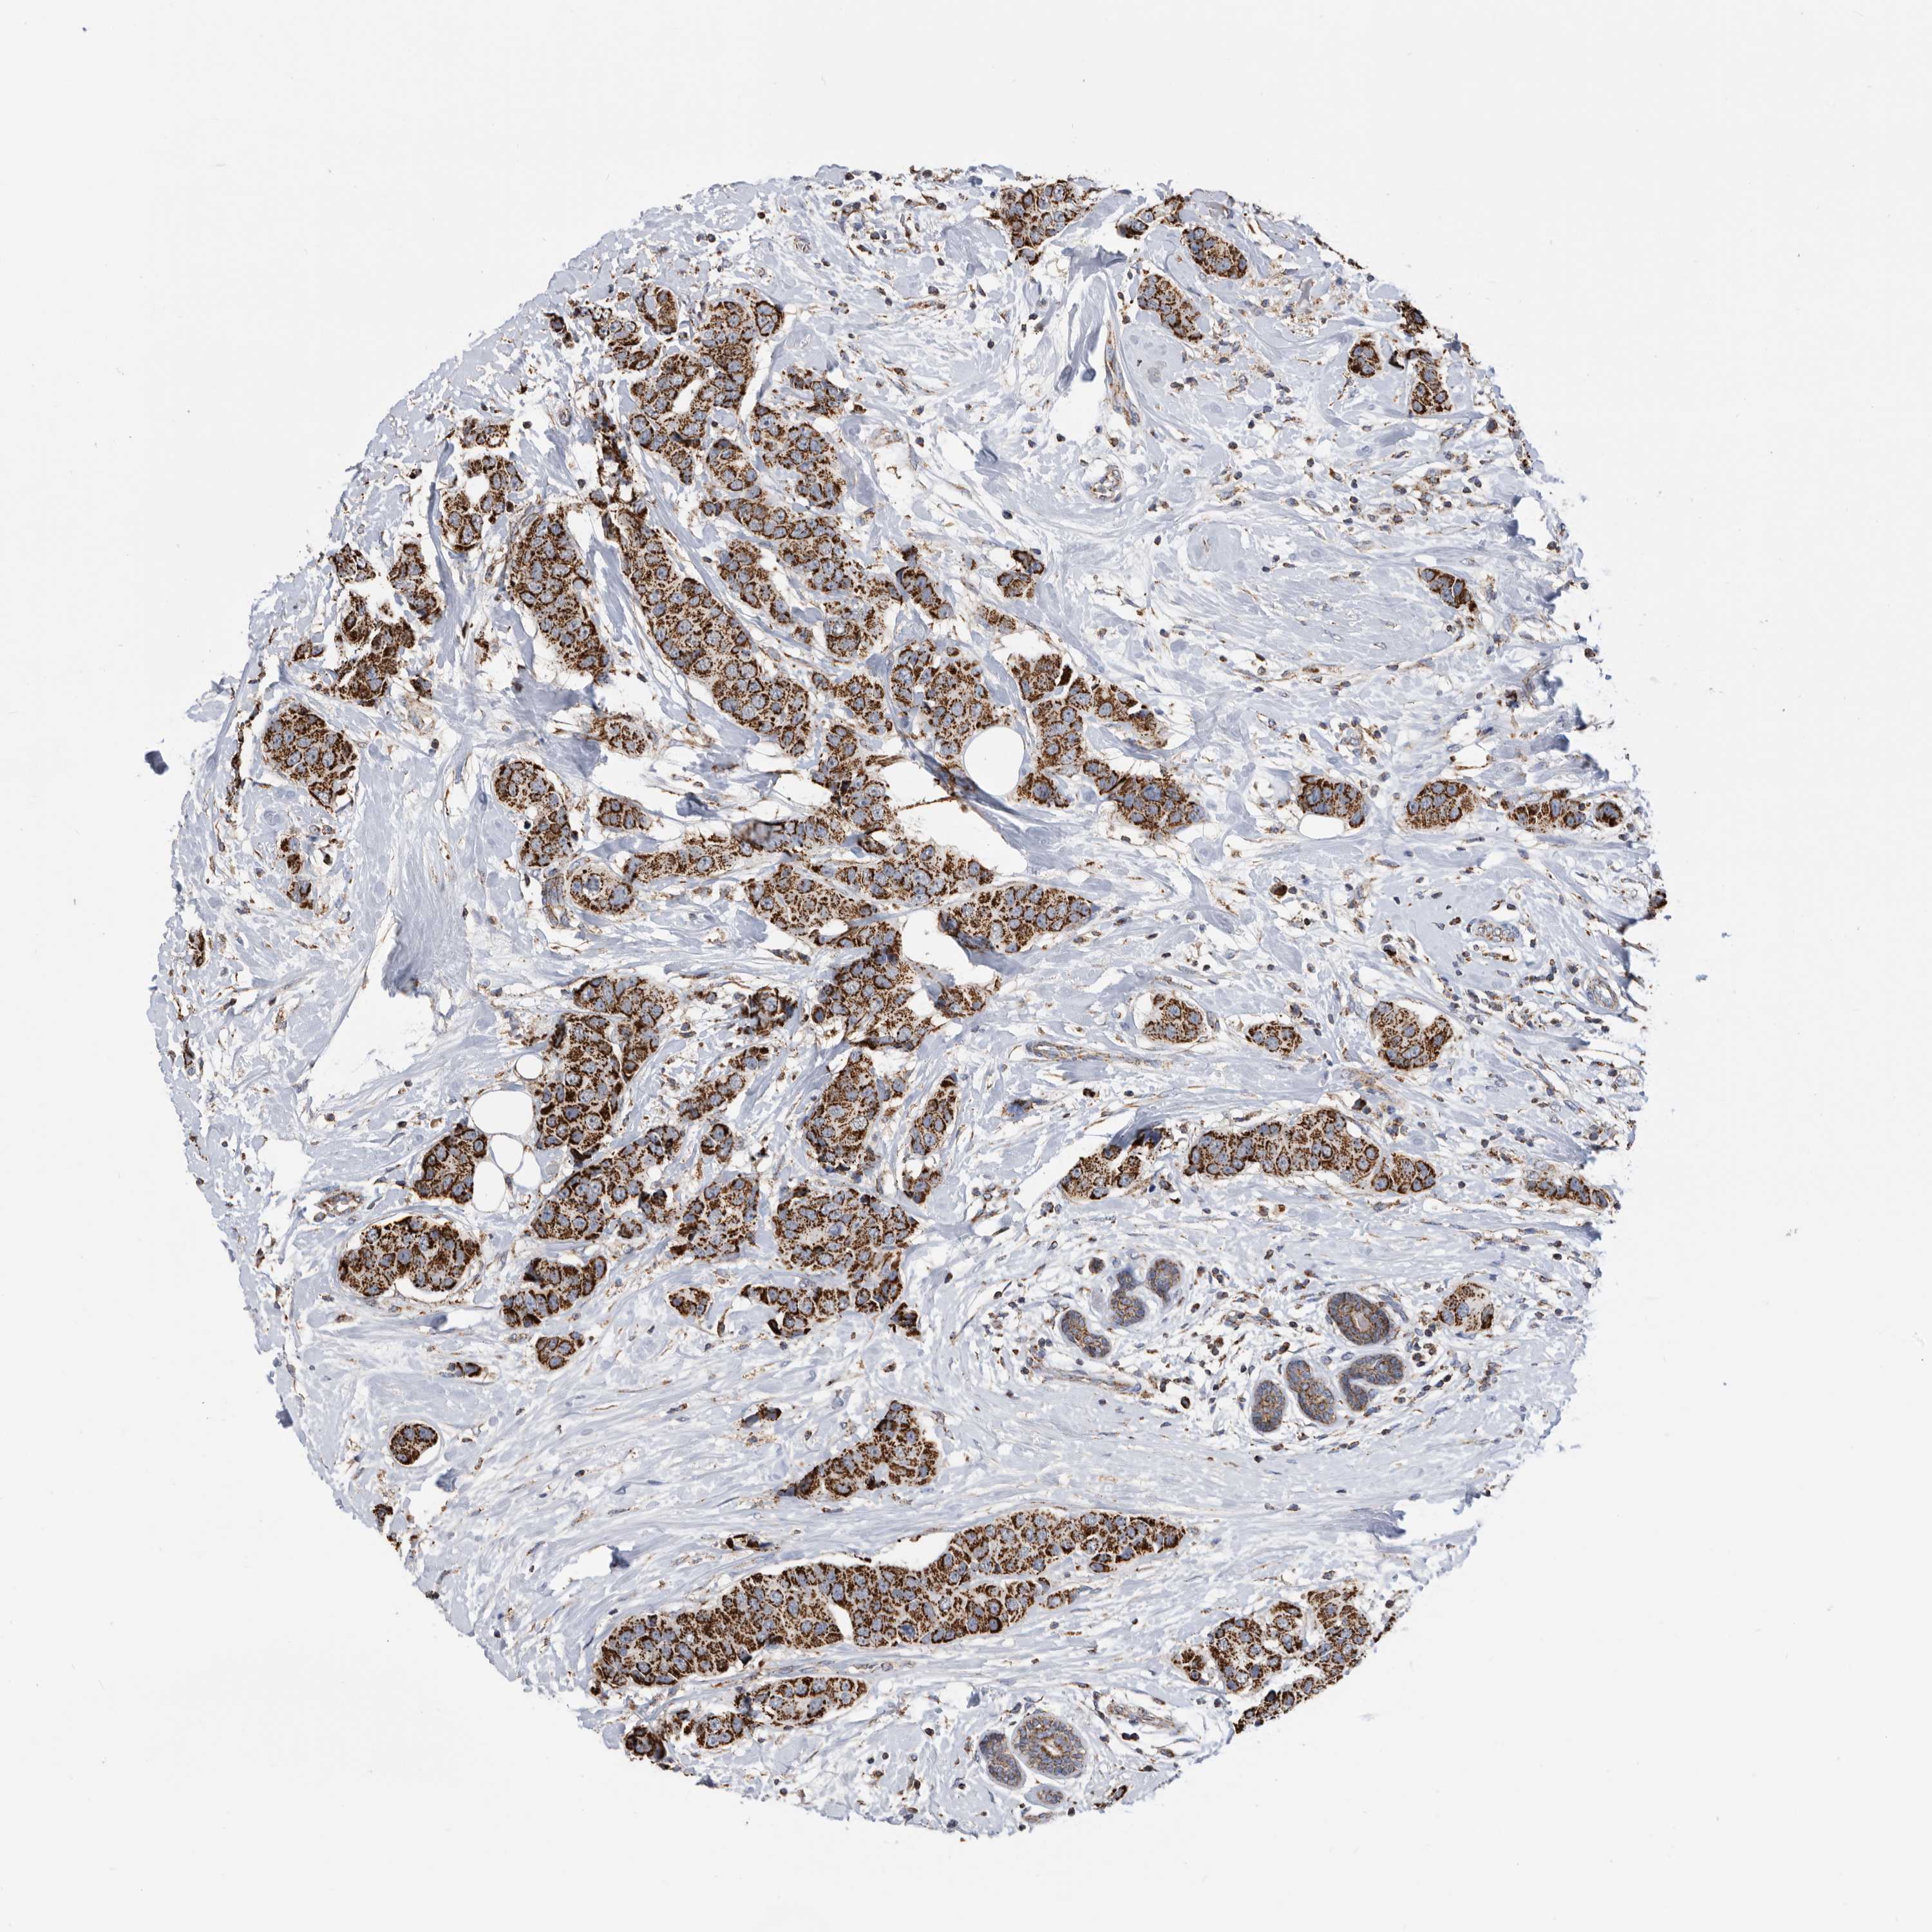

CANCER BREAST CANCER Show tissue menu

BRCA TCGA BRCA VALIDATION PROTEIN EXPRESSION